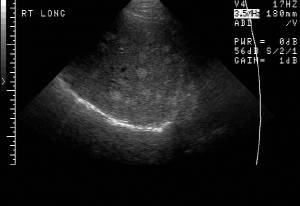

RADIOLOGY: MALE REPRODUCTIVE: Case# 33710: EXAM 1: SEMINOMA OF THE LEFT TESTICLE. EXAM2:. This is a 40-year-old male.

RADIOLOGY: MALE REPRODUCTIVE: Case# 33710: EXAM 1: SEMINOMA OF THE LEFT TESTICLE. EXAM2:. This is a 40-year-old male.